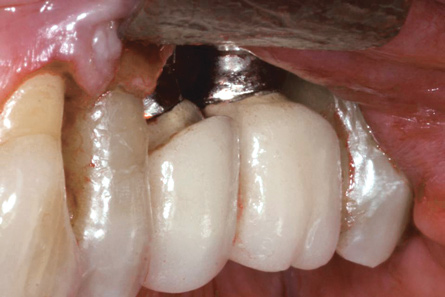

Achieving and maintaining healthy and stable peri-implant soft tissue requires the use of abutment materials that are biocompatible. This in part means using materials that have minimal affinity to bacterial colonization. Differences between titanium and zirconium abutments with regard to bacterial colonization have been of particular interest. Titanium- and zirconia-based surfaces are promptly colonized by bacterial communities similar to those found in adjacent teeth.9,16 Investigations have yielded differing results. A detailed quantitative analysis of an in vitro study found zirconia abutment surfaces have higher biofilm biomass and biofilm diversity than titanium surfaces.17 Figure 1 shows an example of an implant with a zirconia abutment with peri-implantitis.

Fig 1. Implant with zirconia abutment had peri-implantitis that led to gingival recession and exposure of the implant body.

Figure 1